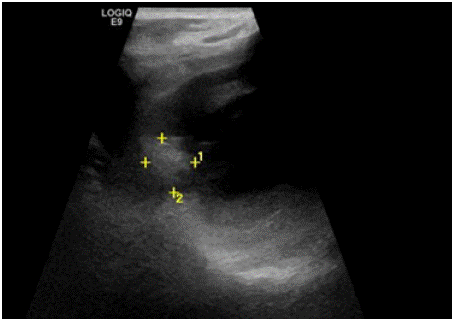

Figure 2: Echocardiography showing a mass in the left atrium.